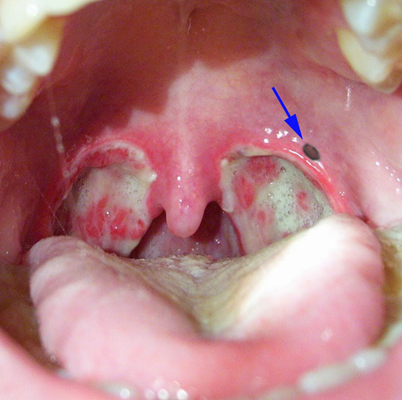

扁桃體週膿腫圖片

扁桃體週膿腫相關文章

扁桃體週膿腫相關問答

A:患者出現扁桃體周圍膿腫,需要進一步做膿腫的穿刺抽膿治療。穿刺抽膿操作前,要使用利多卡因等局麻藥物在穿刺點附近黏膜表面進行局部麻醉,麻藥充分起效後,使用穿刺的粗針頭接注射器,從膿腫的最隆起處刺入,然後抽吸出膿液。要注意穿刺的角度不要太向外側,……

A:扁桃體周圍膿腫也是耳鼻喉科很常見的一個疾病,因為扁桃體感染髮炎形成了周圍膿腫。患者出現咽部異物感、疼痛、口腔有血性分泌物,可以在門診進行切開引流術,切開引流後配合抗生素使用是可以恢復的。這個費用大概需要500塊錢左右,但是要根據當地的消費水……

A:扁桃體周膿腫一旦形成,要膿腫切開引流,加抗炎治療。首先要用注射器穿刺膿腔,抽出膿液,確診膿腫形成。在穿刺點周圍黏膜局麻,用手術刀切開粘膜肌肉,進入膿腔,會有膿液湧出,用大的止血鉗,插入膿腔,擴大膿腔切口,使更多的膿液流出來,同時用注射器,鹽……